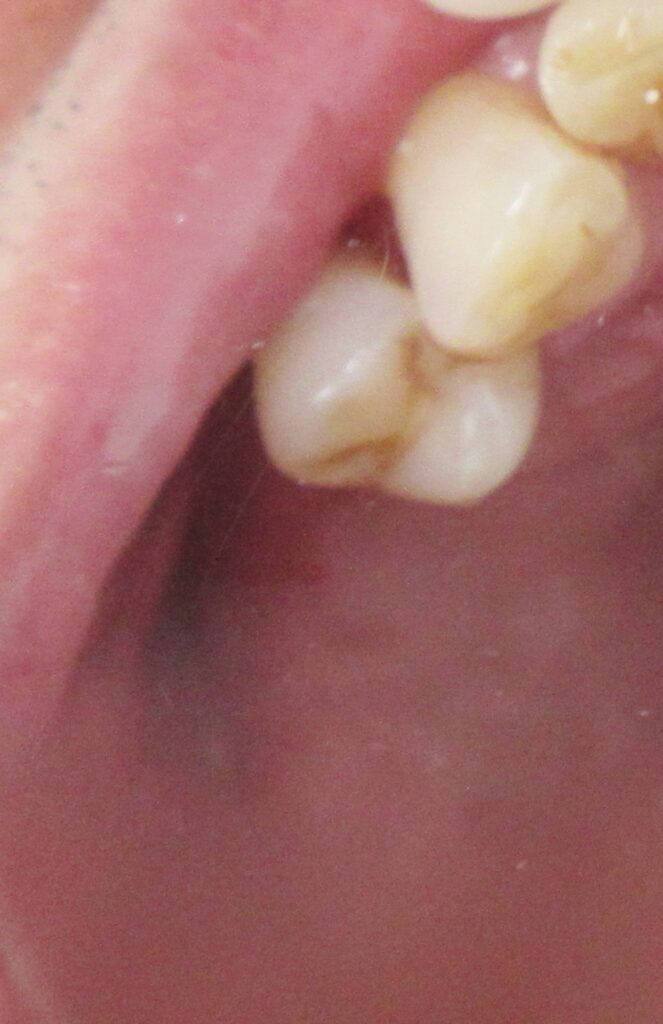

今回の患者様はインプラント植立を希望され、右上5番目・6番目・7番目の3本の植立が決まりました。

まずは右上5番目の歯茎から骨の部分までを穴開けパンチの要領で穴を開けていきます。

くりぬいた部分の歯肉を取り除き、次は骨に穴を開けていきます。